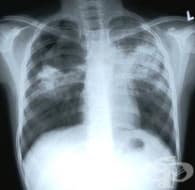

Пулмоналната артериална хипертония (ПАХ) е заболяване, което се манифестира с дискретни симптоми и т...

Идиопатичната пулмонална артериална хипертония (ИПАХ), наричана до скоро първична белодробна хиперто...